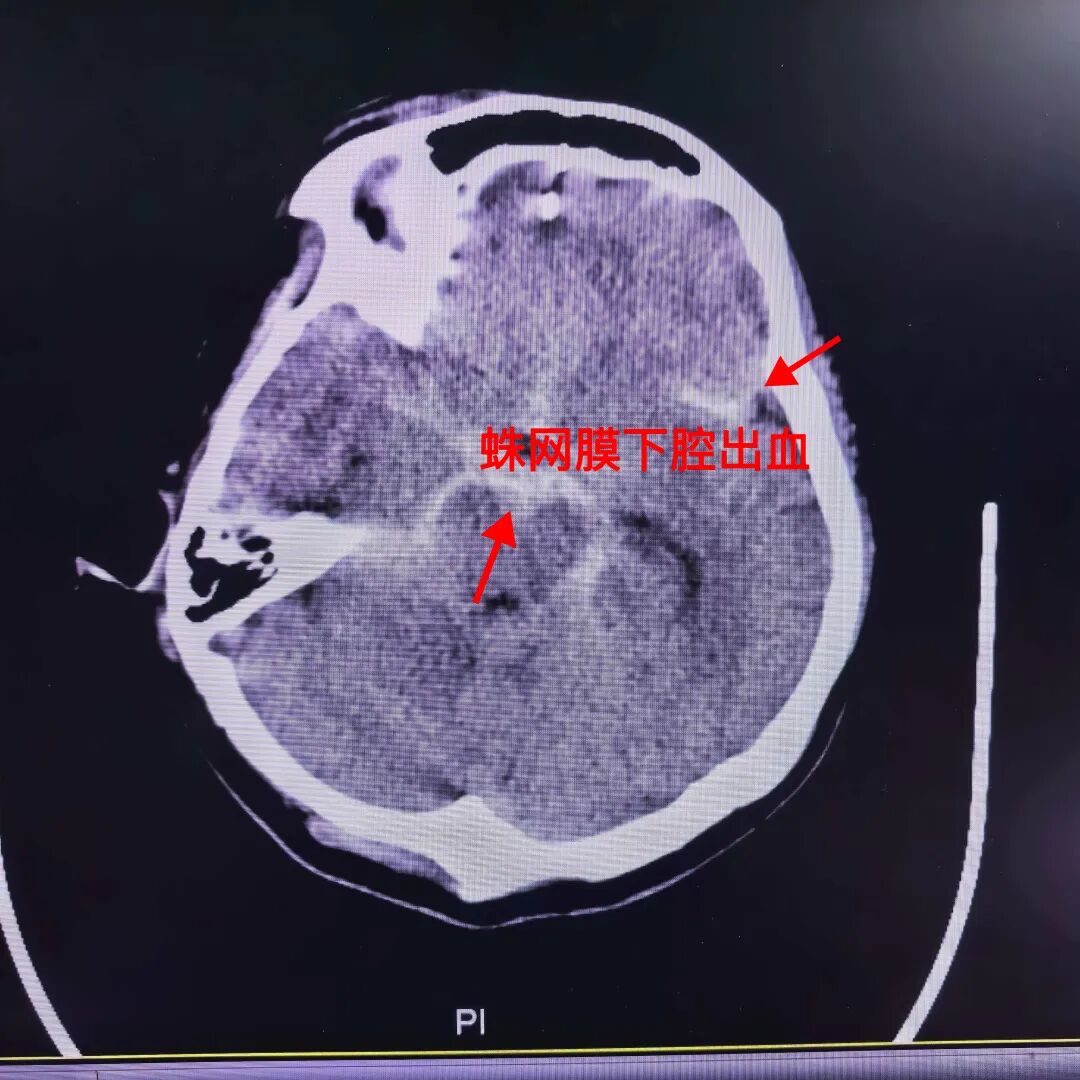

經過緊急檢查,CT結果顯示劉阿姨是 “蛛網膜下腔出血” 。這是什么意思呢?簡單說,就是腦底或腦表面血管破裂,血液流入腦表面間隙里面去。這可是非常危險的腦出血!